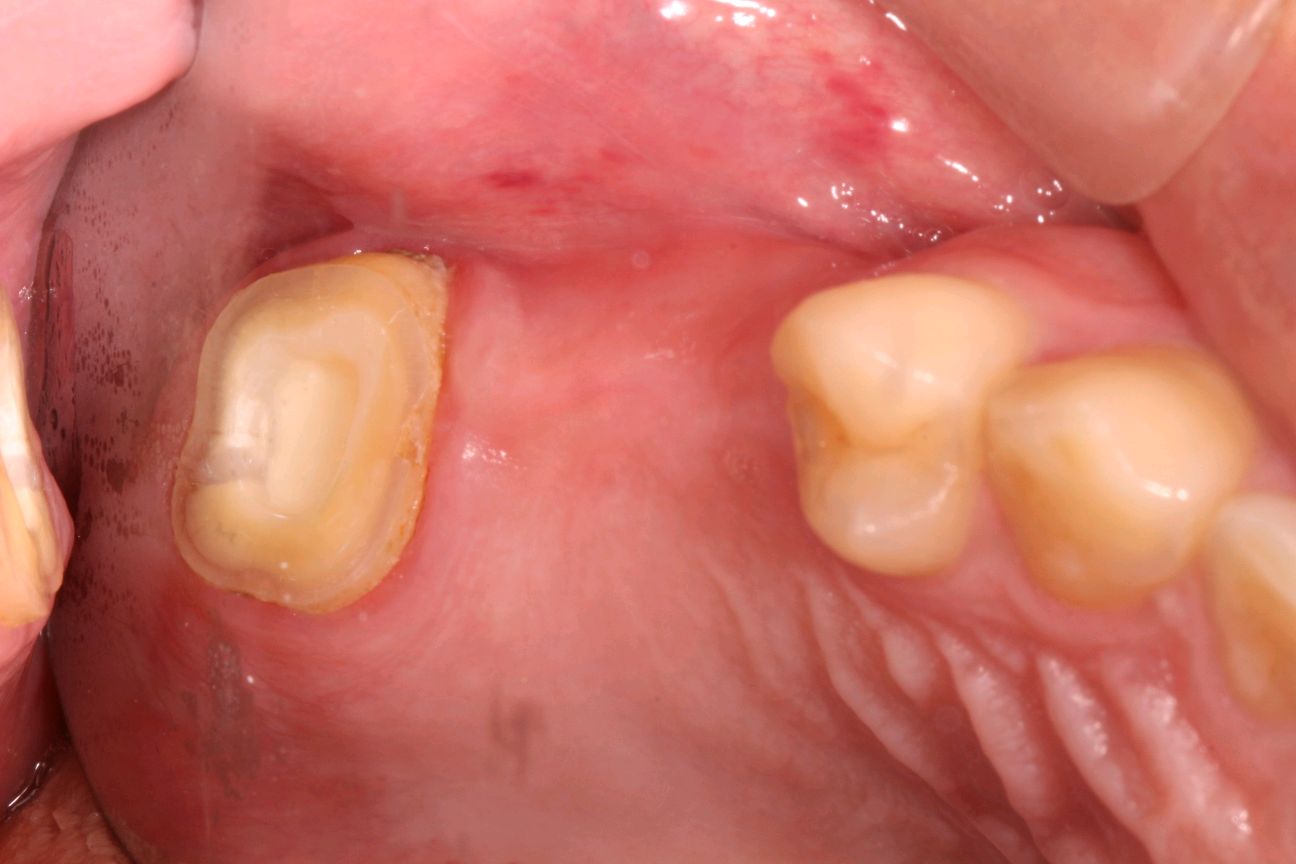

有图有真相:左上7根管治疗后高嵌体修复,采用CERCE扫描、切割、1小时修复完成,实现一次就诊当日修复完成!